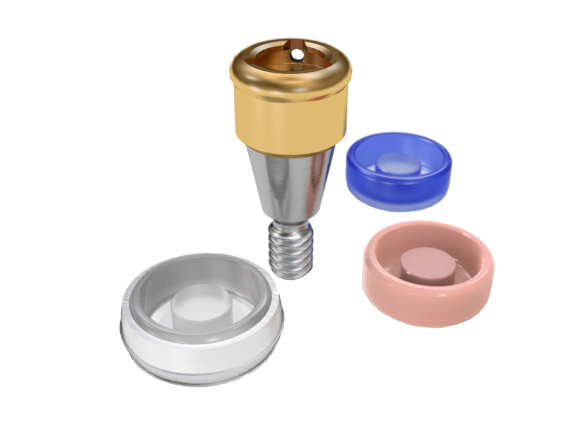

Conical Seal Design – a strong and stable fit

A conical connection that seals off the interior of the implant

from surrounding tissues, minimizing micromovements and microleakage.

Connective Contour – increased soft tissue contact zone and volume

The unique contour that is created when you connect the abutment to the implant.